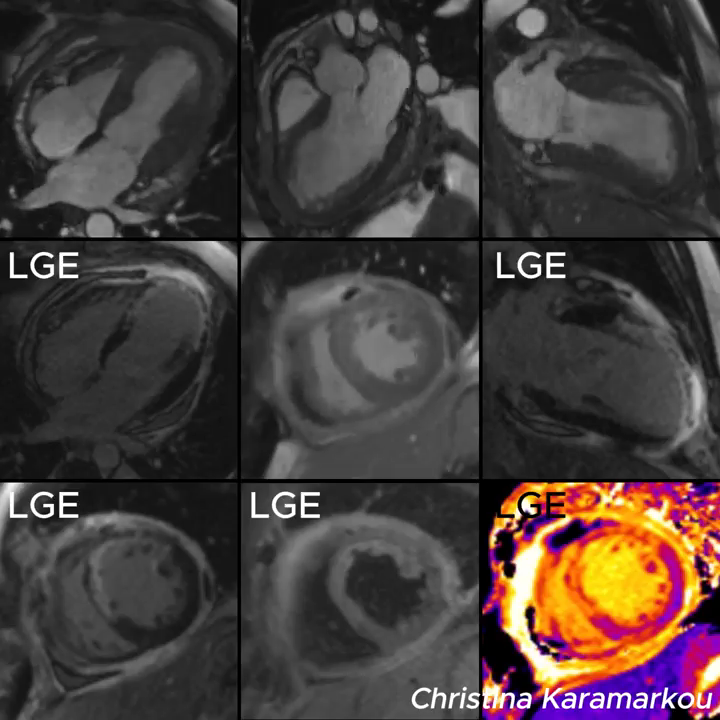

近期看到海外专家 Gonzalo Serrano-Belmar 分享的一个非常实...